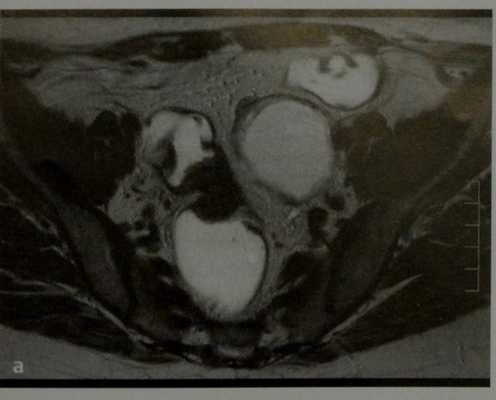

На Т1 и Т2 взвешенных томограммах у пациентки с эндометриозом визуализируются «целующиеся» яичники, расположенные вплотную друг к другу из-за множественных спаек. Также видны небольшая геморрагическая киста в левом яичнике и поверхностная геморрагическая бляшка, дающие гиперинтенсивный сигнал (красные стрелки)